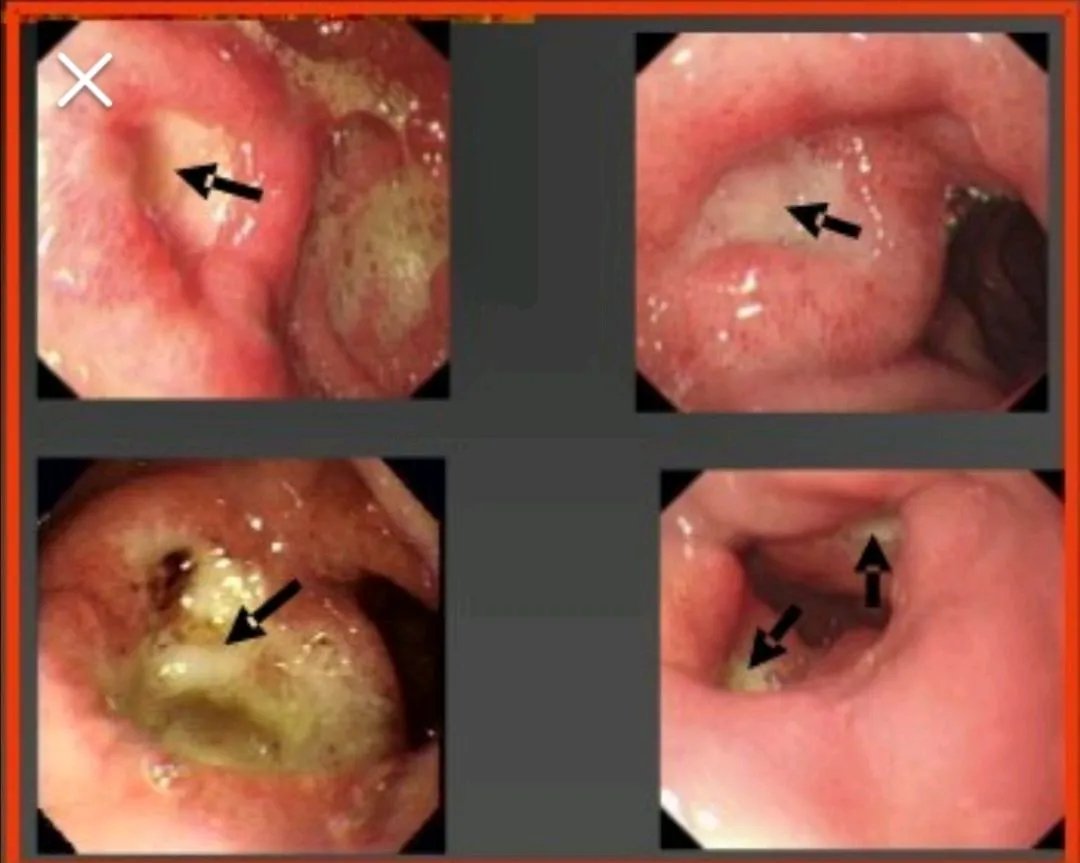

胃镜发现胃溃疡时需要取活检明确溃疡的良恶性,内镜下的表现也可以大概区分:良性溃疡规则,较小,表浅,苔白净,周围黏膜可充血肿胀,周围多无黏膜皱襞隆起,而恶性溃疡大、深,苔污浊,周围黏膜皱襞明显隆起。